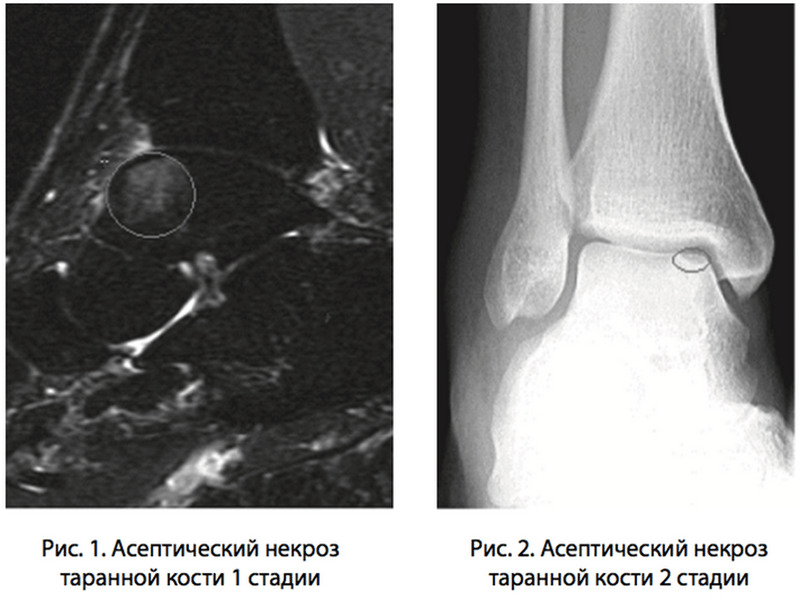

В клинической практике принято выделять несколько стадий изменений таранной кости при аваскулярном некрозе:

- первая стадия характеризуется функциональными нарушениями кровообращения в костной ткани и не имеет признаков органических повреждений кости;

- сохранение нарушения кровотока в области таранной кости приводит к развитию склероза под надкостницей и появлению кист, которые соответствуют областям некроза костной ткани;

- третья стадия, наблюдаемая при значительных изменениях в кости, проявляется деформацией костной ткани с развитием поднадкостничного коллапса;

- четвертая, или терминальная стадия патологии характеризуется выраженной деформацией кости, разрушением хрящевых поверхностей, образованием больших полостей внутри костной ткани. Как правило, подобные изменения полностью необратимы.

Основная задача врачей – выявить заболевание на начальных стадиях его развития, не допустив дегенеративных изменений в кости с ее деформацией.